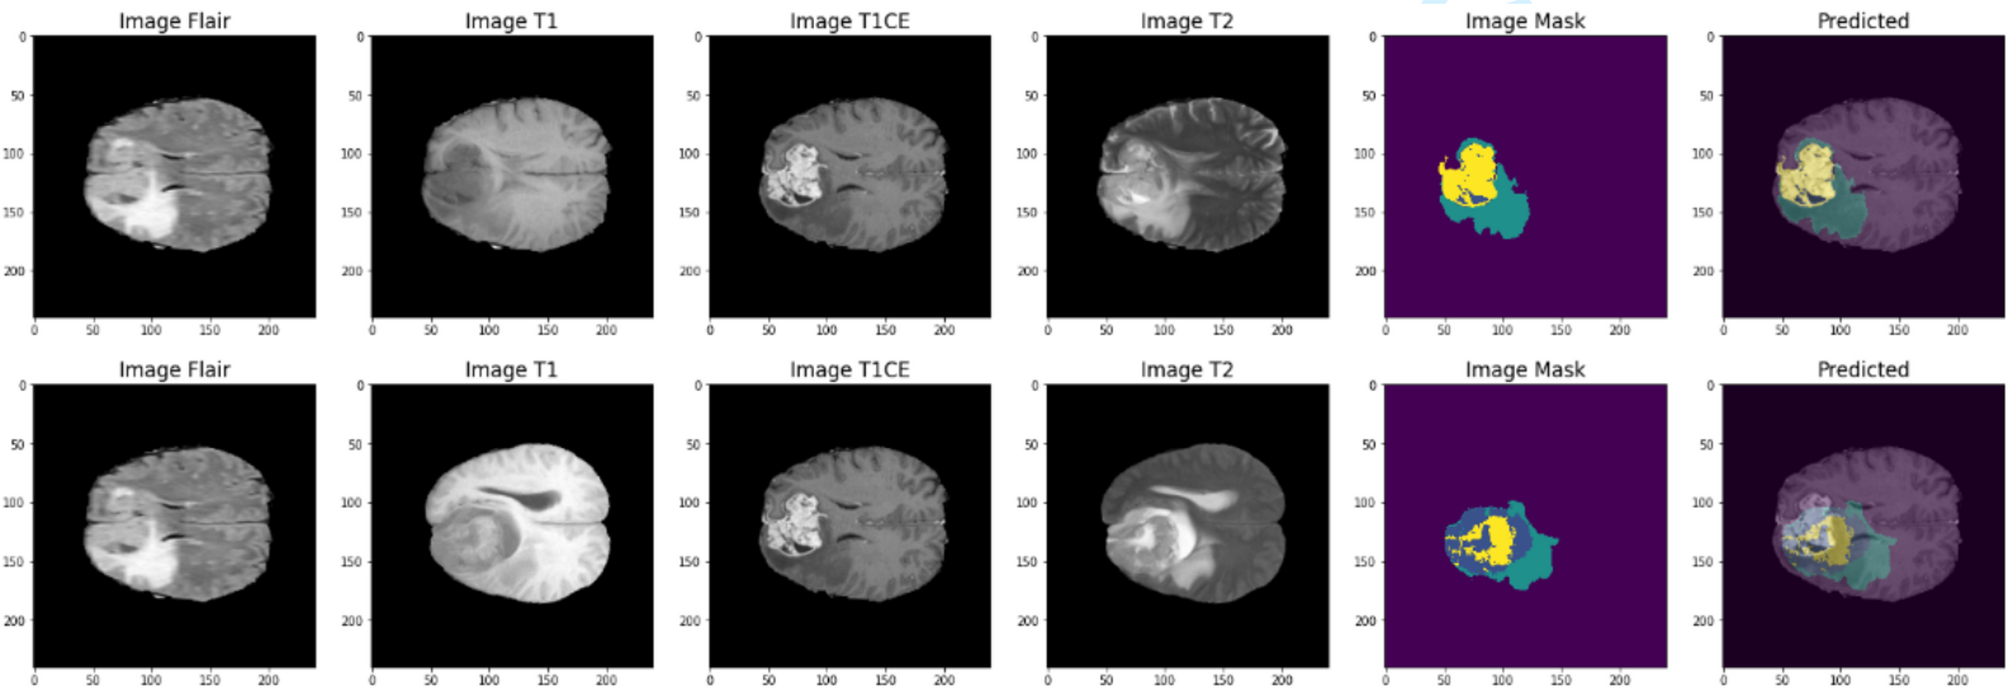

Prediction of brain tumor segmentation using ACU-Net model.